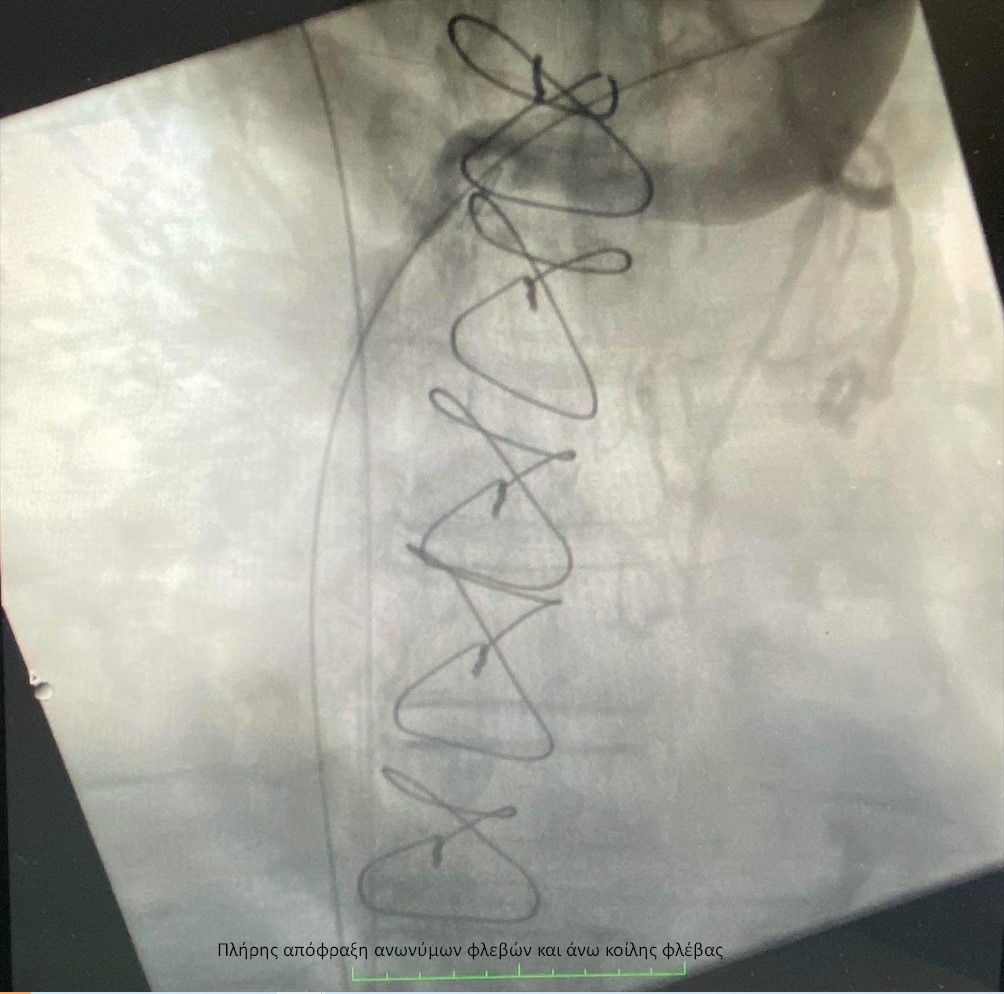

Ασθενής 66 ετών με ιστορικό νεοπλασίας προσήλθε στο ΙΑΣΩ Θεσσαλίας με έντονο πόνο και οίδημα στα δύο άνω άκρα, τον τράχηλο και την κεφαλή. Παρελήφθη άμεσα από την Α΄ Αγγειοχειρουργική Κλινική και του διενεργήθηκε αξονική φλεβογραφία, η οποία έδειξε πλήρη απόφραξη της δεξιάς ανώνυμης φλέβας, νηματοειδή ροή στην αριστερή ανώνυμη φλέβα – λόγω πιεστικών φαινομένων από νεοπλασματικό ιστό – καθώς και εκτεταμένο παράπλευρο δίκτυο στον ανώτερο θώρακα (σύνδρομο άνω κοίλης φλέβας). Εξαιτίας της προχωρημένης κλινικής εικόνας τέθηκε η ένδειξη για ενδοαυλική αποκατάσταση.

Η ομάδα της Α´ Αγγειοχειρουργικής κλινικής υπό την καθοδήγηση του Διευθυντή Αγγειοχειρουργού Νεκτάριου Γαλάνη και την πολύτιμη συνδρομή του Ακτινολόγου Βασίλειου Δημαρέλου και του Αναισθησιολόγου Δημήτριου Ζωσιμίδη, προχώρησε σε αγγειοπλαστική των πλέον στενωτικών σημείων των ανώνυμων φλεβών και της άνω κοίλης φλέβας υπό ακτινοσκοπική καθοδήγηση. Η προσπέλαση ήταν διπλή με παρακέντηση των μασχαλιαίων φλεβών αμφότερων των άνω άκρων και τοποθέτηση δίδυμων στεντ εύρους 12χλστ και μήκους 80χλστ στη δεξιά και αριστερή ανώνυμη φλέβα και την άνω κοίλη φλέβα, που αποκατέστησαν τη βατότητα των ανωτέρω αγγείων.